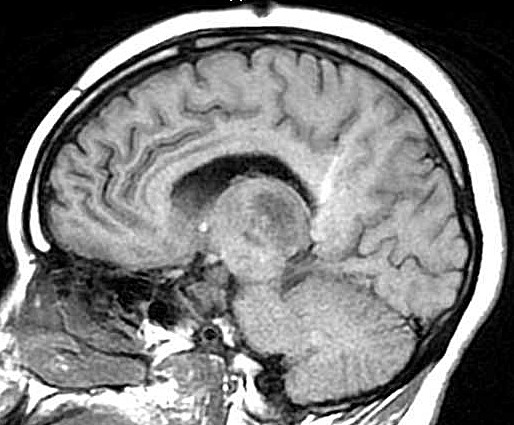

| Fem. 17a. |

| Nódulo sólido homogêneo preenchendo o III ventrículo, com limites precisos, com hipossinal em T1 e hipersinal em T2 e FLAIR, que se impregna por contraste paramagnético. Lesão menor implantada no assoalho do IV ventrículo provavelmente representa disseminação por via liquórica. |

| F. 17a. Tumor teratóide rabdóide atípico de III ventrículo. RM | HE | VIM, GFAP | HHF35, desmina, 1A4 | AE1AE3, EMA |